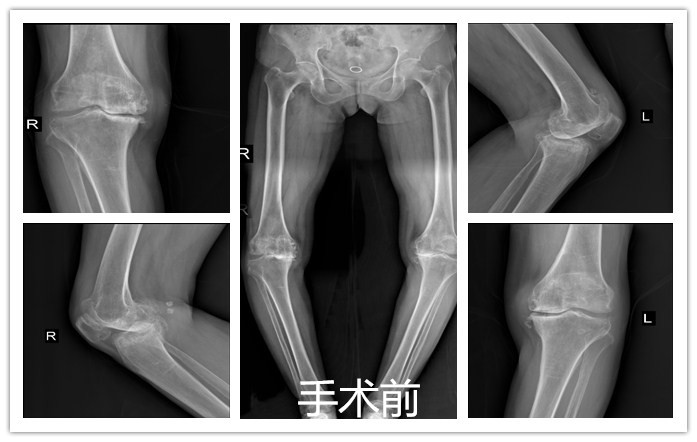

偶然听病友说:西安凤城医院骨科好,还有专门的骨关节专业。就抱着试试看的态度来到我院。经雷永林主任仔细询问病史,详细查体并拍片检查、测量,诊断:双膝关节骨性关节炎。因患者病史时间较长,各种治疗方法都用过了,效果不佳,关节畸形严重,需行人工膝关节置换手术治疗。入院后经积极术前准备,第3天雷永林主任团队为患者一次行双侧人工膝关节置换术。术后麻醉清醒坐起后患者看到双腿伸直了,说这下没有“罗圈腿”了。术后第2天取除引流管后,医生就让下床活动。老太太下床活动后看着腿直直的,走路也好看了,高兴的向医生护士直竖大拇指。